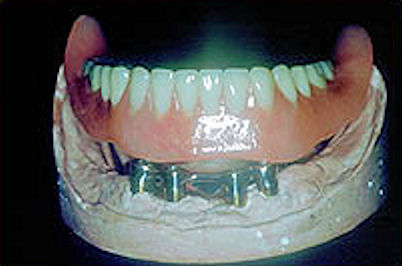

Inside the denture showing the attachments or clips